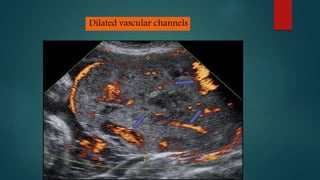

Ultrasound and MRI are used to diagnose placenta accreta, which occurs when the placenta invades the uterine wall due to prior uterine surgery or other risk factors. On ultrasound, signs include low placental implantation, lakes or indentations in the placenta, thinning of the myometrium, disruption of the uterine serosa, and abnormal blood flow on Doppler. MRI may show uterine bulging, a heterogeneous placenta, thinning and interruptions of the myometrium, obliteration of tissue planes, and dark bands within the placenta. These imaging findings help identify placenta accreta and guide management of delivery.